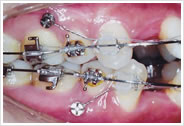

裏側ブラケット

(舌側、リンガル)

歯の裏側につける矯正装置です。舌側ブラケット、リンガルブラケットとも呼ばれます。目立たずに矯正を行うことができますが、医師の技術により仕上がりに差が出るといわれています。